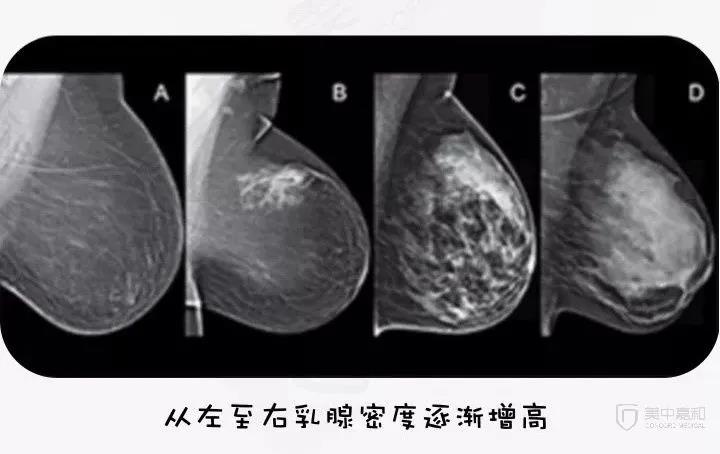

美国放射协会将乳腺分为4型:

脂肪型(乳腺大部分组织为脂肪)

少量腺体型

多量腺体型

致密型(乳腺大部分组织为腺体,非常致密)

最新的研究表明,致密型乳腺相比脂肪型乳腺,具有更高的乳腺癌发病率。

另外一个事实上,在中国,超过50%的女性具有致密型乳腺,且致密型乳腺在胸小的女性中更为常见。